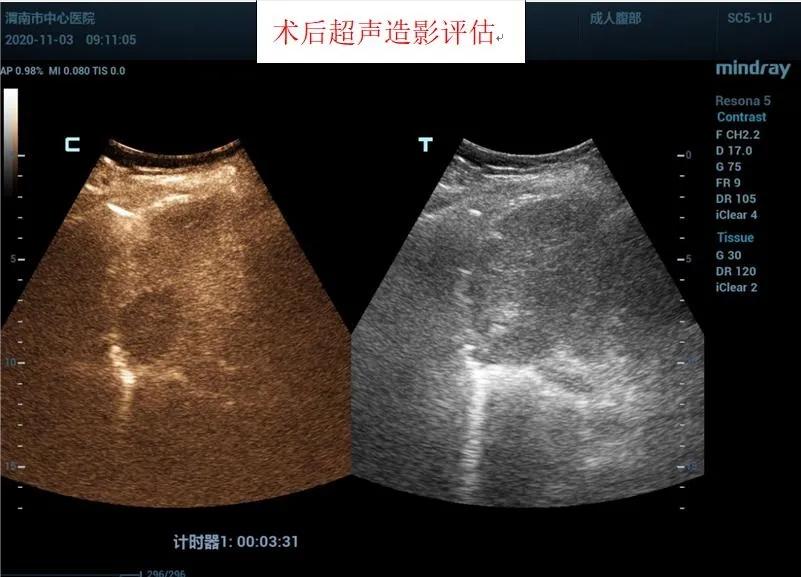

在王建宏教授的指导下,华玺副主任医师、韩婷婷主治医师的默契配合下,经过20余分钟,手术顺利完成,术后安返病房。术后3天超声造影进行评估,显示消融处呈无增强,提示达到预期治疗效果且患者精神状态良好。

据超声科刘晓晖主任介绍,超声造影技术联合微波消融术可以在术前更明确的反映肿瘤病灶的实际大小及其浸润范围,可将微波治疗范围以超声造影测值作为参考,从而更客观的判断肿瘤病灶大小及周围浸润情况,确认需治疗的范围,同时可以使用超声造影在微波消融术中进行检测引导,术后通过超声造影确认肿瘤是否完全灭活。该方法与传统外科手术相比创伤小,手术时间短,术中痛苦小,并发症极少;术后恢复快,缩短了住院时间,乐鱼手机站入口超声科将超声造影技术与微波消融术联合使用,为患者带来了新的治疗希望。